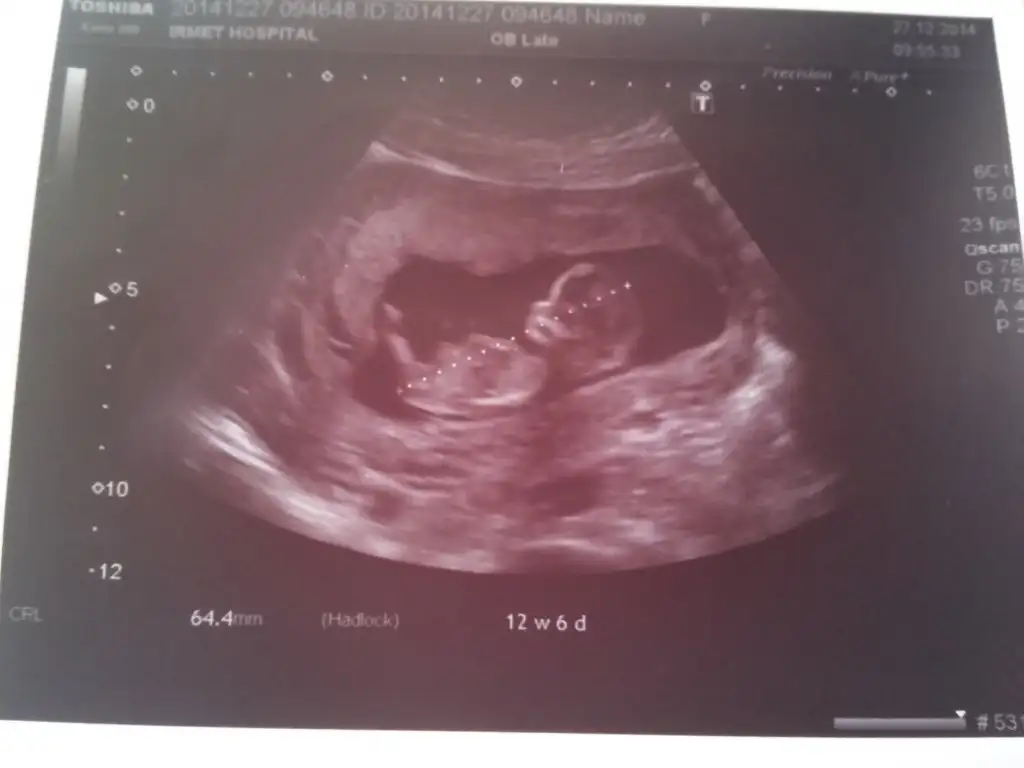

13+3 doktorun fikrini bugün söyledi ama sizde görün istedim bi bakar misiniz

Kızlar yorum lutfennnnnnn lutfen bu yavrunun cinsiyeti ne tahmin yürütün yokmu başka yorum yapannn. Belli olunca yollicam size doktorum 12 haftalık ve 13+ 4 te aynı yorumu yaptı lutfen yorumlarınızı bekliyorum .:((((